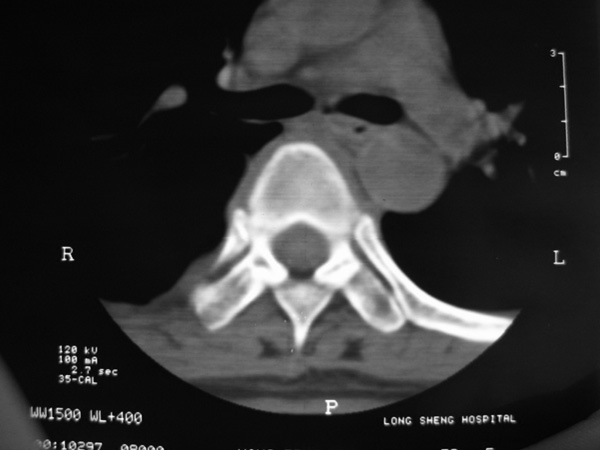

女,45岁,胸背部疼痛2个月。t6、7胸椎病变。

椎旁肿胀的软组织内可见气泡影,对脊柱的化脓性和结核性的鉴别有帮助吗?

胸椎结核伴冷脓肿形成且侵入椎管。

胸椎结核与脊柱椎体化脓性脊柱炎,从影像特点很难鉴别,本例具有二者的共性特点,建议结合临床鉴别以下,我考虑:1 化脓性脊柱炎.2 胸椎结核.原因:1 椎旁脓肿内含气泡.2 椎体溶骨性破坏,但未见死骨.

胸椎体骨质破坏伴死骨形成,椎周环状软组织肿胀,范围较长,考虑胸椎结核伴冷脓肿形成。鉴别;1转移性肿瘤;椎弓根骨质破坏多见,软组织肿块局限。椎间隙尚存。有原发肿瘤病史。2,淋巴瘤;骨质破坏 然骨皮质轮廓线尚存,当椎管骨示环状软组织影时有一定特异性。病变较局限。建议mri增强,观察冷脓肿与软组织肿块很有帮助。

胸椎结核与脊柱椎体化脓性脊柱炎,从影像特点很难鉴别,本例具有二者的共性特点,建议结合临床鉴别以下,我考虑:1 胸椎结核.2 化脓性脊柱炎.原因: 椎体溶骨性破坏,但未见死骨.我认为大家说的气泡是假象。